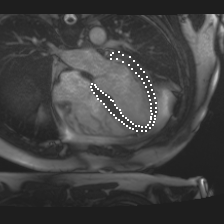

Accurate segmentation and motion estimation of myocardium have always been important in clinic field, which essentially contribute to the downstream diagnosis. However, existing methods cannot always guarantee the shape integrity for myocardium segmentation. In addition, motion estimation requires point correspondence on the myocardium region across different frames. In this paper, we propose a novel end-to-end deep statistic shape model to focus on myocardium segmentation with both shape integrity and boundary correspondence preserving. Specifically, myocardium shapes are represented by a fixed number of points, whose variations are extracted by Principal Component Analysis (PCA). Deep neural network is used to predict the transformation parameters (both affine and deformation), which are then used to warp the mean point cloud to the image domain. Furthermore, a differentiable rendering layer is introduced to incorporate mask supervision into the framework to learn more accurate point clouds. In this way, the proposed method is able to consistently produce anatomically reasonable segmentation mask without post processing. Additionally, the predicted point cloud guarantees boundary correspondence for sequential images, which contributes to the downstream tasks, such as the motion estimation of myocardium. We conduct several experiments to demonstrate the effectiveness of the proposed method on several benchmark datasets.